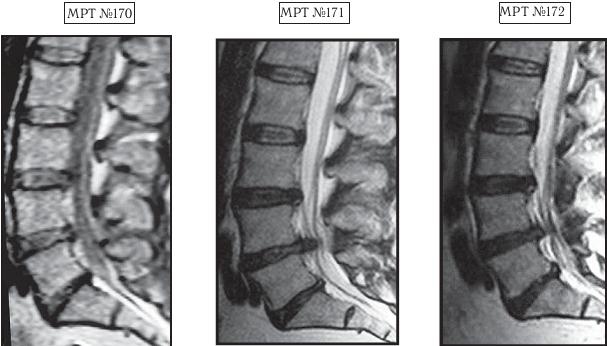

На МРТ № 170 наблюдается состояние поясничного отдела позвоночника: ретроспондилолистез LV (соскальзывание позвонка относительно другого позвонка), протрузии межпозвонковых дисков в сегментах LII—LIV и LIV-LV

На МРТ № 171 наблюдается состояние поясничного отдела позвоночника: ретроспондилолистез LV увеличение протрузии межпозвонкового диска в сегменте LIII-LIV, образование секвестрированной грыжи межпозвонкового диска в сегменте LIV-LV с разрывом задней продольной связки, абсолютный стеноз на этом уровне.

На МРТ № 172 — состояние поясничного отдела позвоночника в середине первого курса лечения методом вертеброревитологии (после двух недель от начала лечения): наблюдается положительная динамика, выраженная ретрузия секвестра грыжи межпозвонкового диска в сегменте LIV-LV, визуально прослеживается увеличение высоты межпозвонкового диска в том же сегменте, что свидетельствует о начавшемся активном процессе его восстановления, значительное уменьшение стеноза спинномозгового канала на данном уровне.

В этот же день, когда больного привезли ко мне на приём, я взялся за эту работу. Через две недели лечения методом вертеброревитологии данный пациент смог самостоятельно приезжать на автомобиле (за рулём). По своей инициативе он сразу сделал ещё одно МРТ (результат интересный, МРТ № 172), на котором можно наблюдать процесс обратного движения грыжи, то есть когда фрагменты выпавшего межпозвонкового диска «заходят» обратно в межпозвонковый диск. Другими словами — процесс ретрузии секвестра грыжи межпозвонкового диска в сегменте LIV-LV а также активный процесс восстановления самого диска.